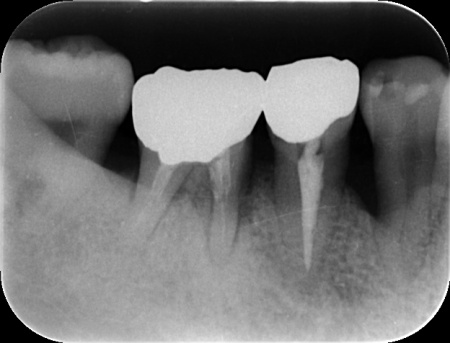

| カウンセリング | 拝見したところ、右下の奥歯(第1大臼歯)に歯根破折が確認でき、これが痛みの原因だと考えられます。 歯根破折をそのまま放置すると、歯を支える骨の吸収が進んだり周囲の歯茎が炎症を起こしたりする可能性があります。 そこで、レントゲン検査などで詳しく確認した結果、ひびは根の深い部分まで達しており、残念ながら歯を温存することは困難です。 また、その手前の小臼歯は、過去の治療で装着した詰め物の下で虫歯が再発する二次カリエスが見つかりました。このまま放置すると虫歯がさらに広がる可能性があります。 以上のことから、右下の大臼歯は抜歯後に欠損を補う治療、手前の小臼歯は虫歯の再治療が必要と診断しました。 |